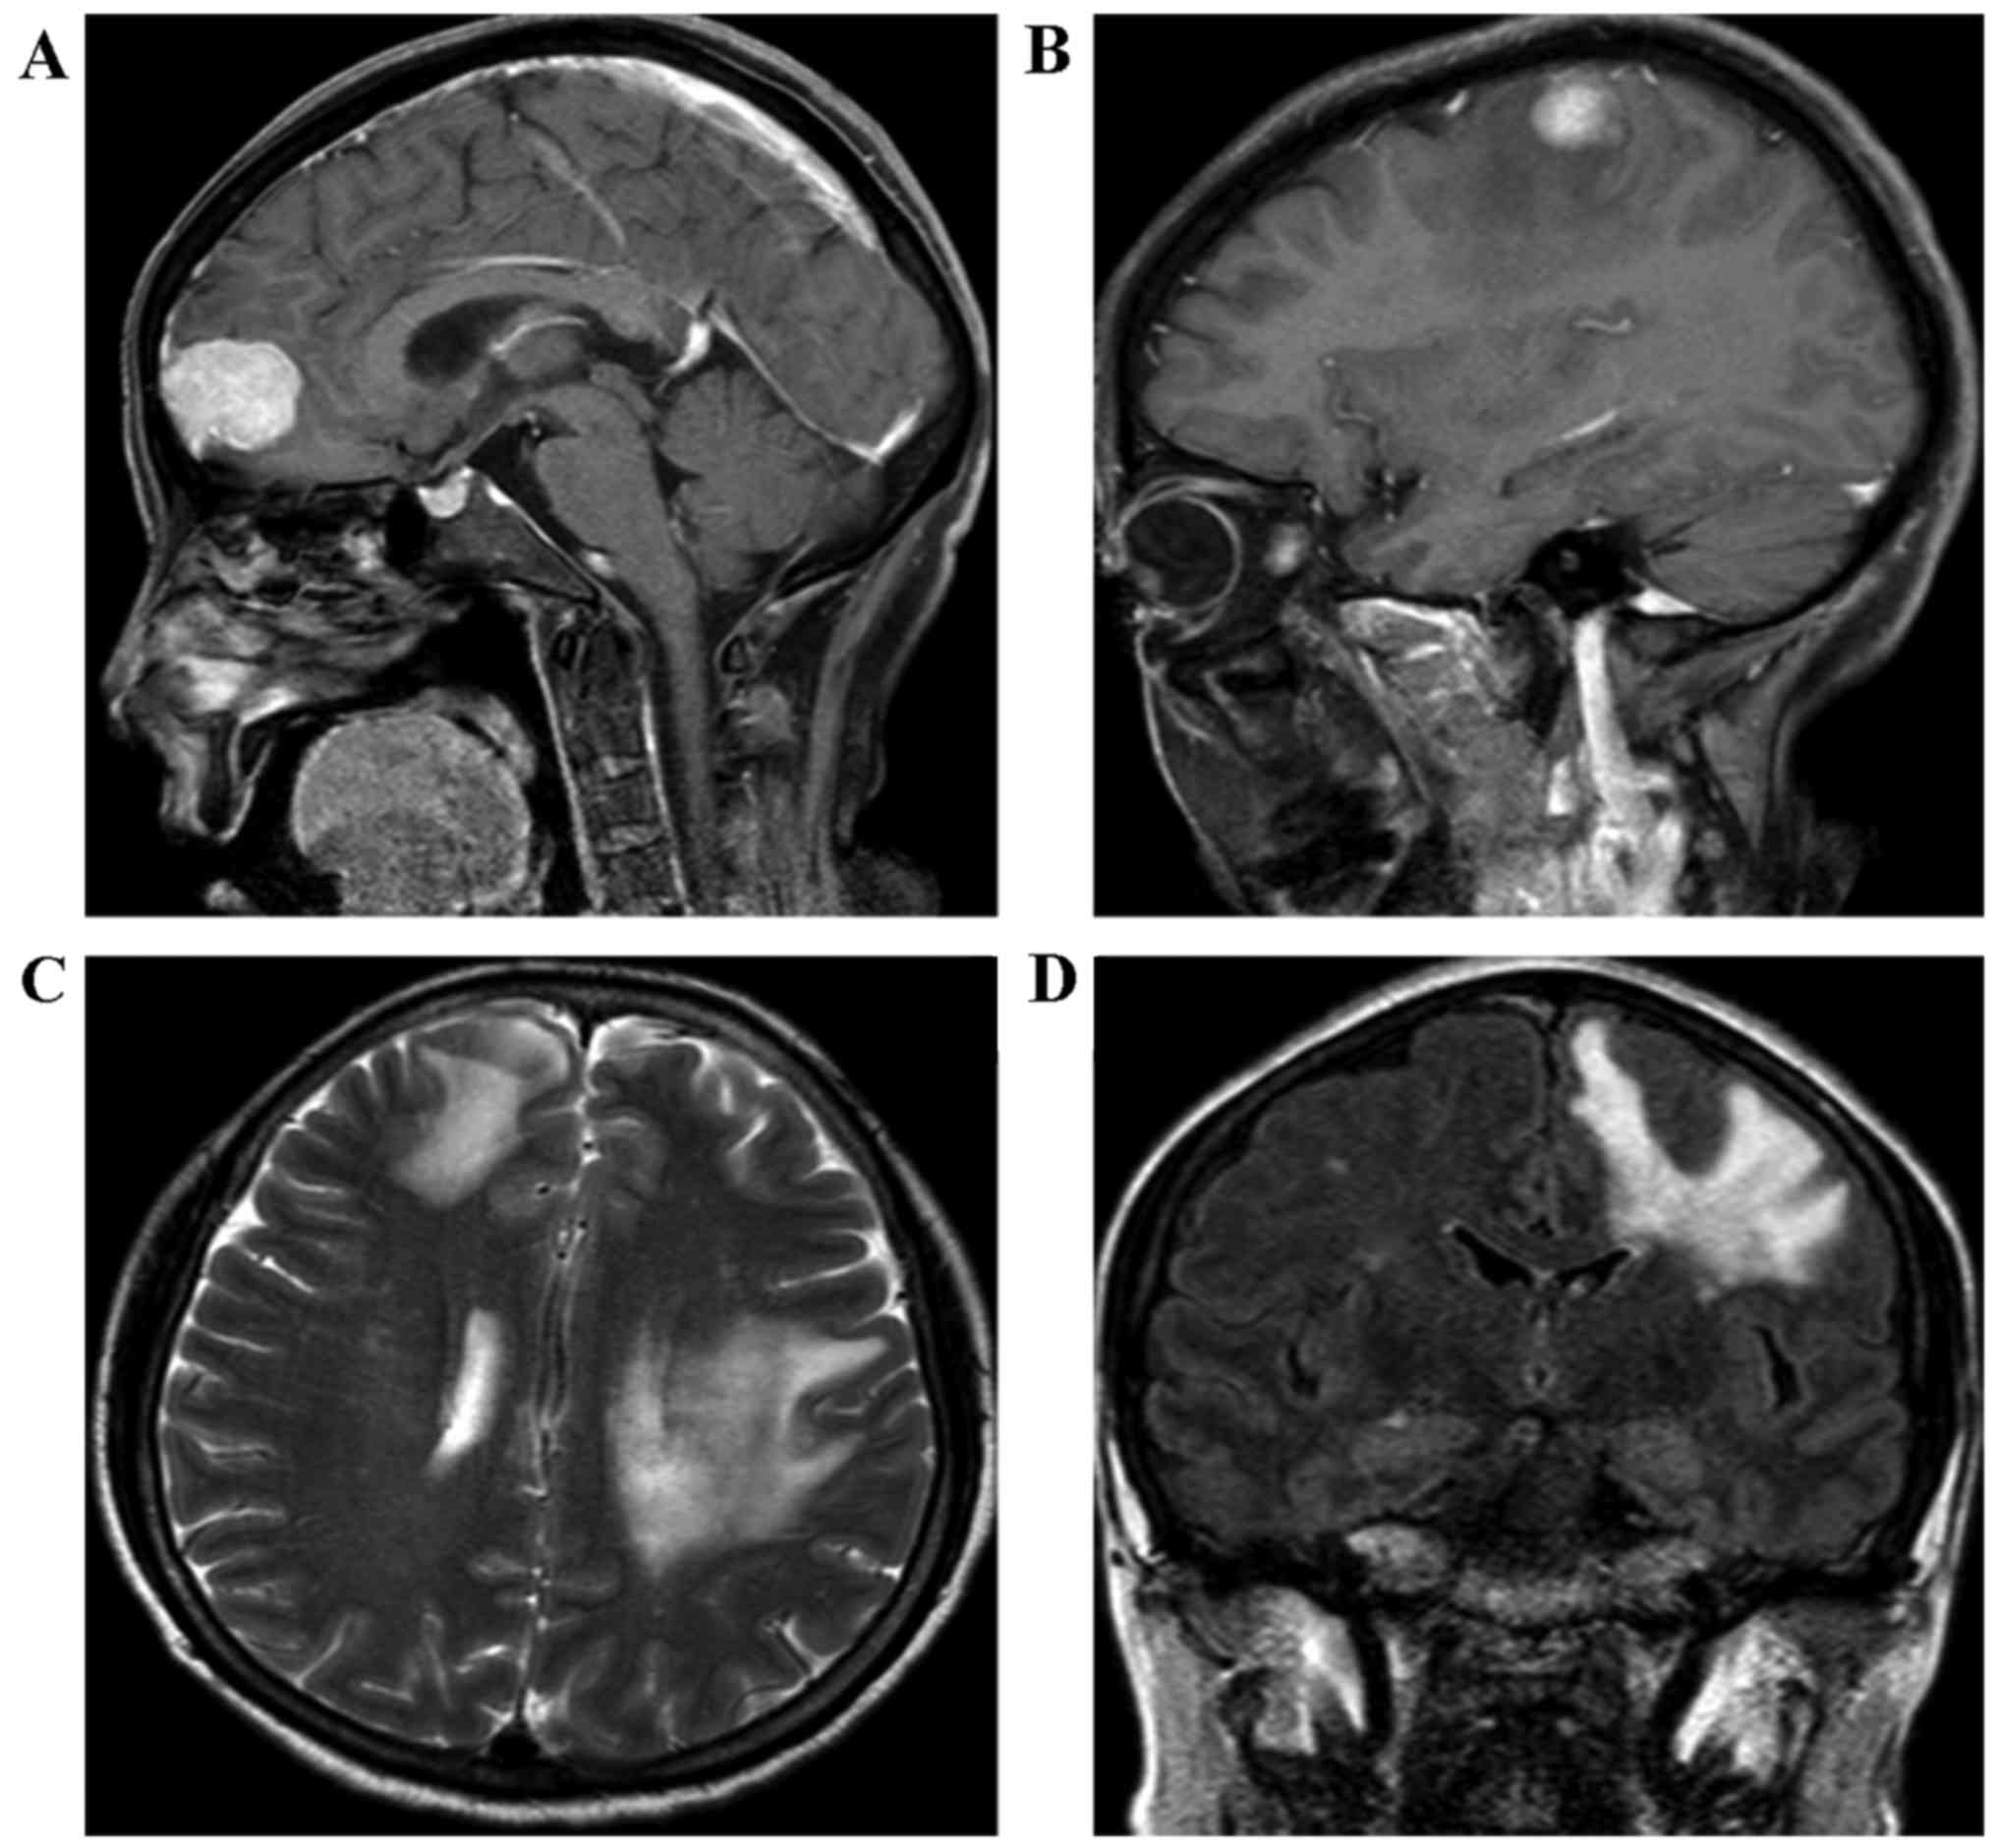

During the following-up, the level of the biomarker, CEA, was determined to be 3.2 ng/ml and the CA19-9 concentration was 32.6 U/ml 3 months after the initial radical surgery, which suggested that the patient was disease-free and that no tumor recurrence activity had been identified. The patient remained alive for 14 months without any tumors, and neither abdominal computed tomography (CT) nor a laboratory examination revealed any sign of tumor recurrence. Subsequently, the patient felt weakness of the right upper extremity and presented with mildly epigastric distention, as well as nausea, 15 months after the initial surgery. Therefore, the patient was readmitted to the Sun Yat-sen Memorial Hospital, Sun Yat-sen University, Guangzhou, China. A physical examination was unremarkable. Laboratory tests revealed that the level of aminotransferase was moderately increased, the level of CEA was 9.2 ng/ml, and the concentration of CA 19-9 was 207 U/ml. Furthermore, the cerebral MRI displayed enhancing lesions of the right subcortical frontal lobe and the left subcortical parietal cortex lobe (Fig. 2). It was clearly indicated that these small tumor entities were surrounded with flaky edema (Fig. 2B-D), which is a feature of metastatic encephaloma. Our multidisciplinary team discussed the presentation of the cerebral MRI images, and the radiologist and neurosurgeon considered that they were consistent with metastatic tumors, rather than a primary tumor of brain. At the same time, neither tumor recurrence nor locoregional lymph nodes metastasis was detected in the abdomen using contrasted CT (Fig. 3). A neurosurgeon was consulted for possible biopsy prior to chemotherapy or radiotherapy, but the patient refused to accept any further medical therapy. She died suddenly from a brain hernia due to progression of brain metastasis 2 months after the isolated brain metastasis.

Figure 2.

The MRI of the brain revealed an enhancing lesion of the right subcortical frontal lobe (A) and of the left subcortical parietal cortex lobe (B), respectively, 15 months after curative resection. (C and D) Lesions in the transverse and coronary position are displayed, respectively. MRI, magnetic resonance imaging.

Although, in the present case study, the diagnosis of isolated brain metastases was a clinical diagnosis made without biopsy due to the refusal of the patient, it was observed that the CEA concentration of 9.2 ng/ml (normal concentration, ≤5 ng/ml) and the CA19-9 concentration of 207 U/ml (normal, ≤34 U/ml) were markedly abnormal. Comparing these values with the CEA level of 3.2 ng/ml and the CA19-9 level of 32.6 U/ml recorded 3 months after radical surgery, this suggested that HCCA recurrence had occurred to a large extent. Furthermore, the additional primary tumor of the alimentary tract was excluded on the basis of past history and abdominal image workup. Importantly, multiple lesions, but not only one tumor entity, were detected by the brain MRI scan. In addition, these small tumor entities were surrounded with clearly flaky edema (Fig. 2B-D), which is a feature of metastatic encephaloma.